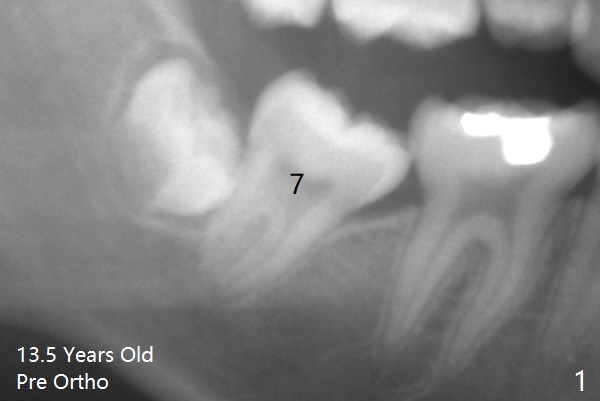

A 13.5-year-old man with crowding and L7s' mesial tilt (Fig.1).